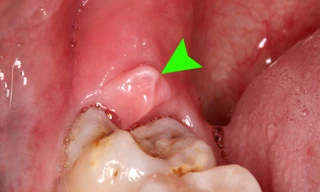

TPO - Răng số 8, còn gọi là răng hàm số 8 (răng khôn) - là những chiếc răng mọc cuối cùng của mỗi người và thường mọc khi bước vào lứa tuổi trưởng thành, trong độ tuổi từ 17 tới 25 tuổi. Tuy nhiên có trường hợp phải nhổ răng số 8 mọc lệch để bảo vệ sức khỏe răng miệng và sự an toàn của những chiếc răng lân cận.

Nhổ răng khôn là một việc mà rất nhiều người sẽ phải đối mặt sau 20 tuổi, tuy nhiên, có những thời điểm cần tránh đi nhổ răng vì có thể dẫn đến những biến chứng gây ảnh hưởng lớn tới sức khỏe.